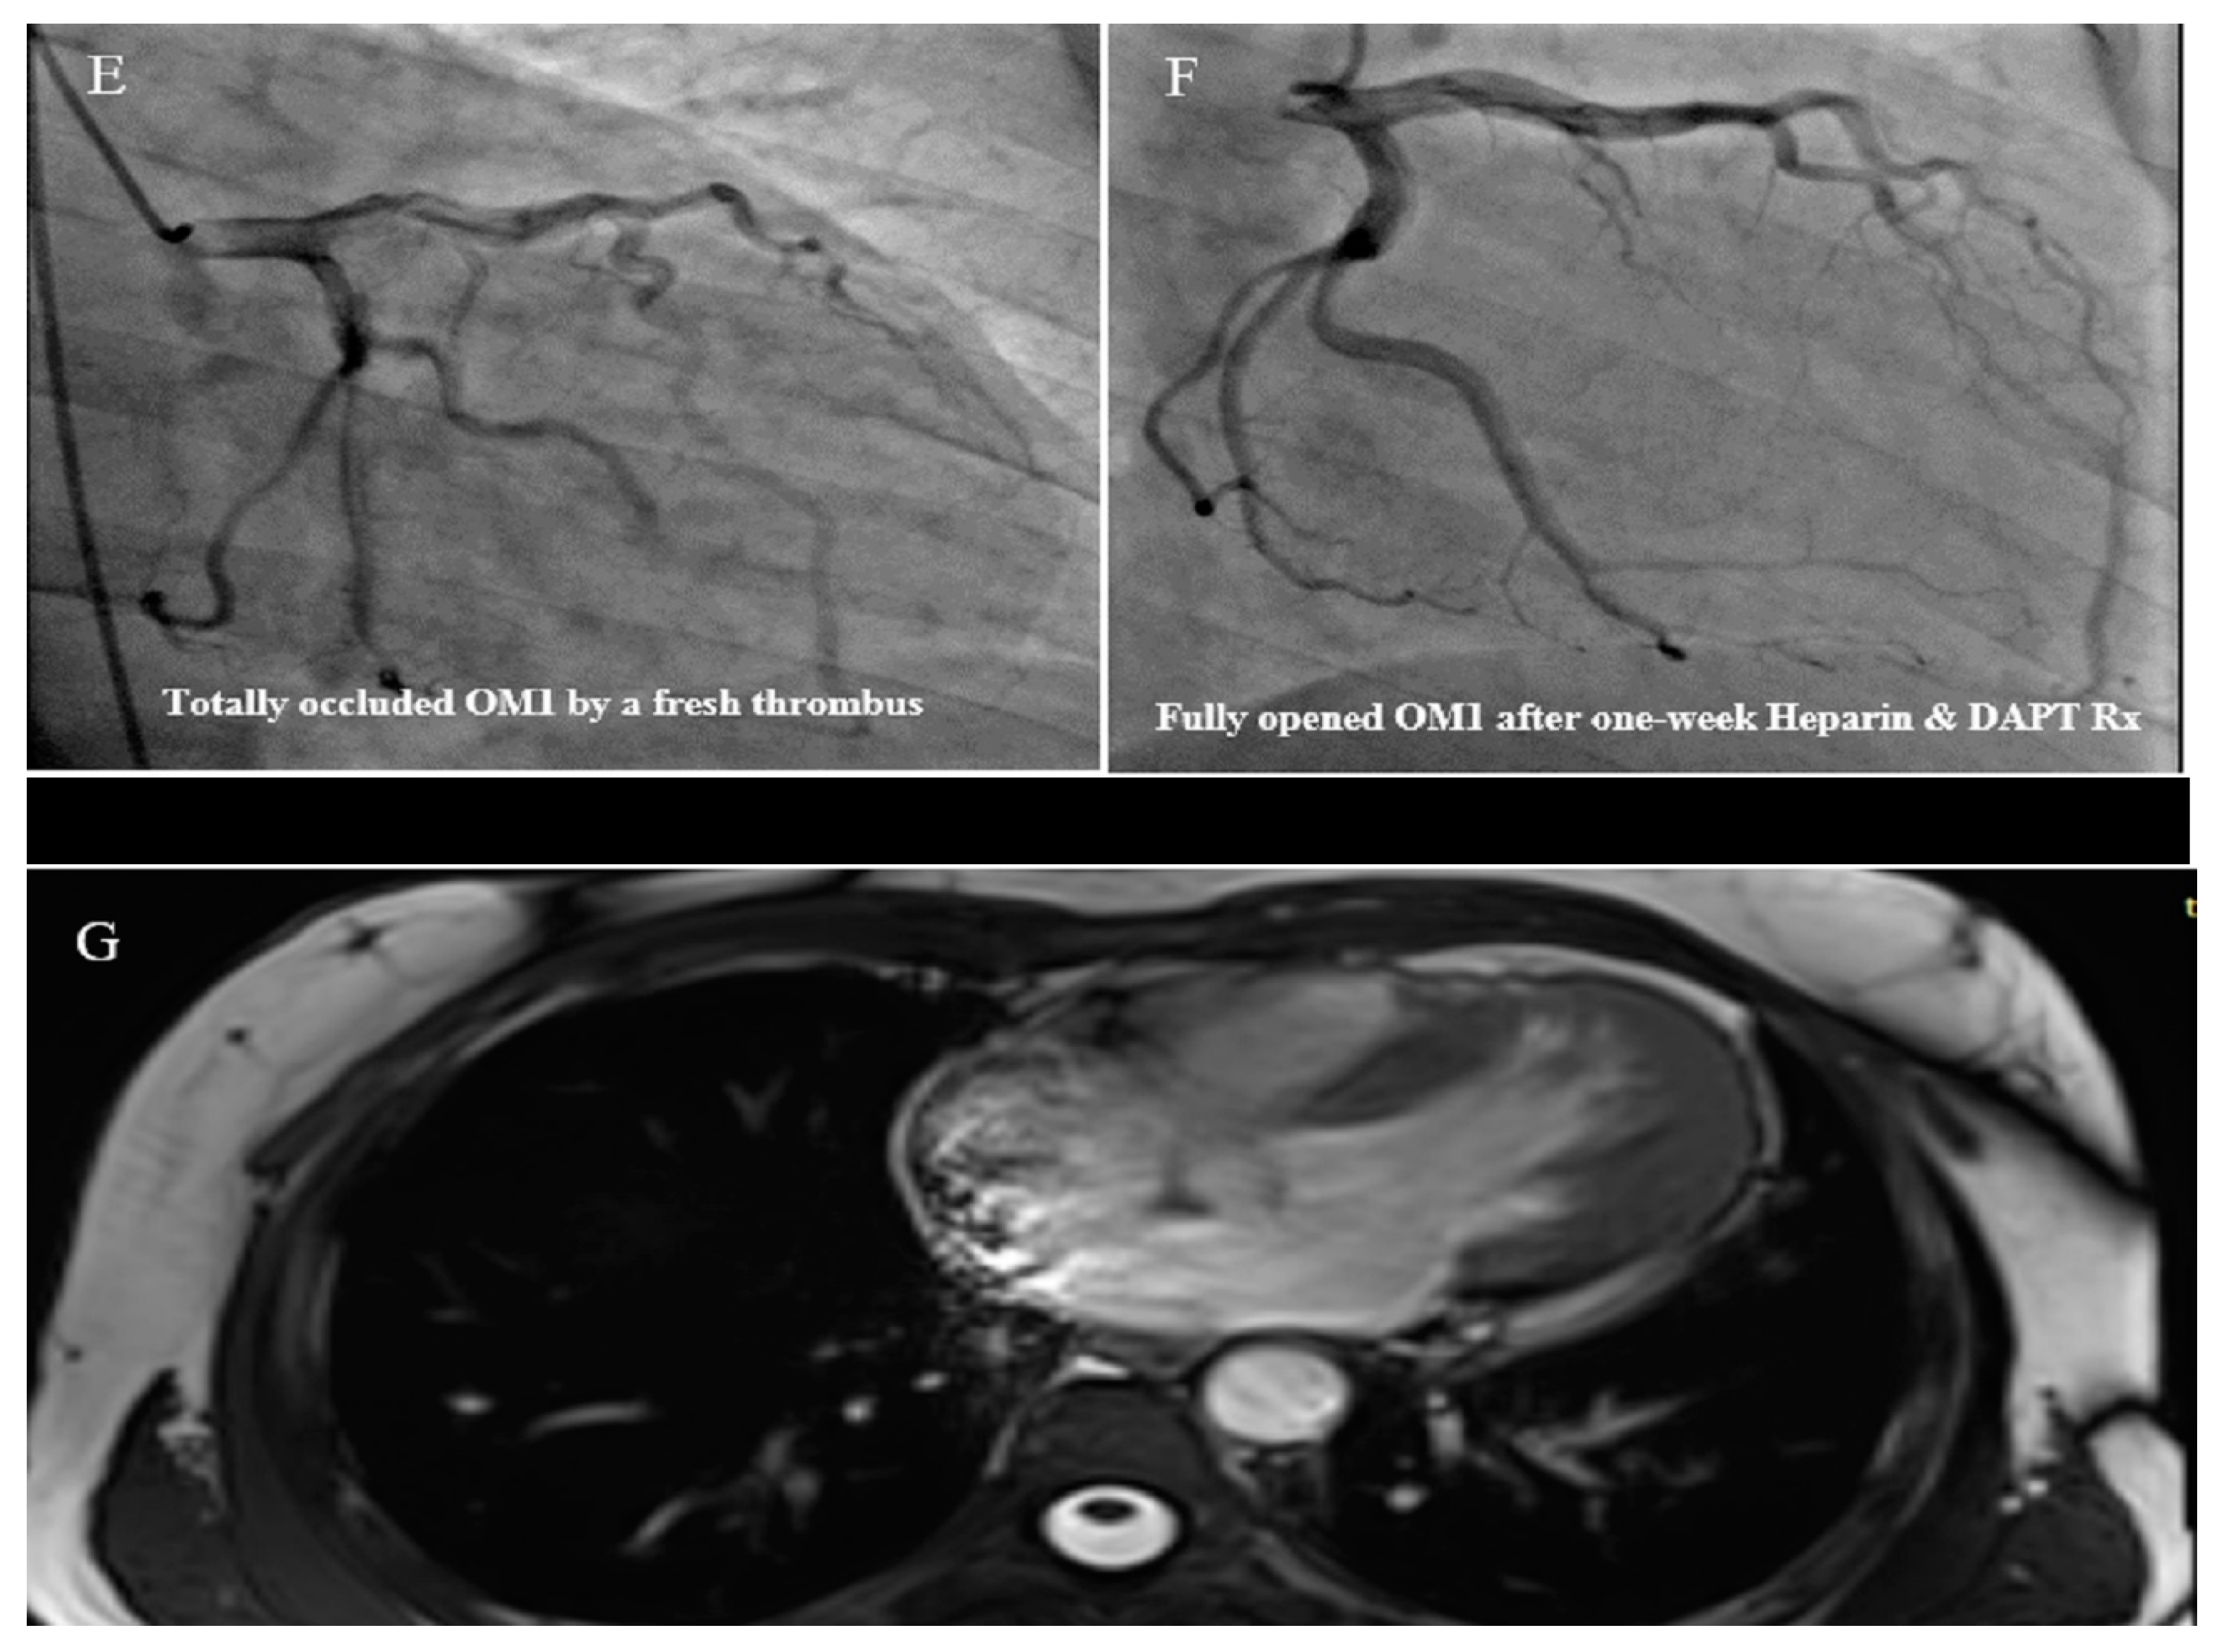

2.3. Case #3. NCLV with Aortic Dilation Complicated by Coronary Embolism

A 37-year-old gentleman with no history of cardiac disease and major CVD risk factors presented with acute retrosternal pain with radiation in both shoulders since 3 h prior to admission to the emergency department, accompanied by profound cold sweating and nausea, though there was no vomiting. On arrival, the ECG showed ST-segment elevation in the inferolateral leads, and diagnostic coronary angiography revealed a filling defect in the second obtuse marginal branch, in favor of occlusion by a fresh thrombus. He spent his hospital course uneventfully with response to anticoagulation plus dual antiplatelet therapy for 2 weeks (opened occlusion on the second angiography) and was discharged after 3 days in stable condition. Because of the possibility of the cardiac source of embolization, TTE and TEE were performed, which revealed NCLV with normal left ventricular ejection fraction (LVEF = 55%) and no obvious thrombus, in addition to mild aortic dilation (ascending aorta diameter = 42 mm; indexed = 22 mm). STE showed reduced global longitudinal strain (GLS = −11%). Moreover, CMR confirmed the diagnosis of NCLV (Figure 3). A genetic study showed two heterozygous mutations in the SCNIB and ALPK3 genes. The family screening was performed, and his mother had an undiagnosed isolated NCLV with the same genetic results, as well. The patient was prescribed warfarin and was symptom free at the follow-up visit.

Figure 3.

Two-dimensional transthoracic echocardiographic views of case #3. (A); Left ventricular apical SAX view, illustrating hypertrabeculated apical portions in addition to deep intertrabecular recesses. (B); Color Doppler echocardiography, showing evidence of direct blood flow from the ventricular cavity into deep intertrabecular recesses. (C); Dilated aortic proximal ascending aorta. (D); Speckle tracking echocardiographic findings, compatible with myocardial performance impairment of all segments with GLS = −14.3%. (E,F); Coronary angiography showing on arrival and 2-week post-treatment results. (G); Cardiac magnetic resonance imaging, illustrating prominent non-compaction in left ventricular apical and lateral wall.